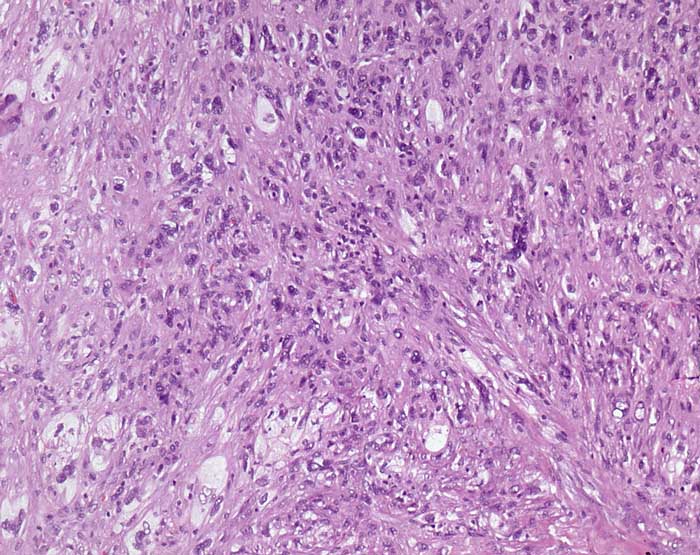

PathoPic ID 7777 - malignes fibröses Histiozytom

malignes fibröses Histiozytom

maligner Tumor

Subkutis

Haut

Solider Tumor mit ausgesprochener Pleomorphie. Mehrkernige Zellen. Eine spezifische Pigmentierung ist nicht erkennbar.

Subkutaner Tumor.

Histologie

100

49

männlich